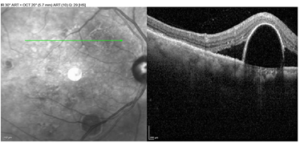

Optical coherence tomography (OCT) images were acquired OU. While center macular thickness, measuring 248 microns OD and 238 microns OS, and foveal contour were normal OU, multiple extrafoveal PEDs corresponding with the lesions noted on fundoscopy were visualized on the scans. Of note was a large PED with overlying SRF that was approximately 0.75 disc diameters in size and located superonasal to the macula OD (Figures 1 and 2). An additional PED of approximately the same size was present just inferior to the macula, and a third, smaller PED was visualized temporal to the macula OD. OS images revealed a few small PEDs in the superior, inferior and temporal macula, none of which were associated with SRF (Figure 3). All PED findings on OCT were consistent with serous PED, which typically appears dome-shaped and well-delineated with an elevated, hyper-reflective RPE overlying a hyporeflective and optically empty space.2,8,9

![]() Figure 1. Optical coherence tomography scan and gray-scale image of pigment epithelial detachment with surrounding subretinal fluid in the right eye. |